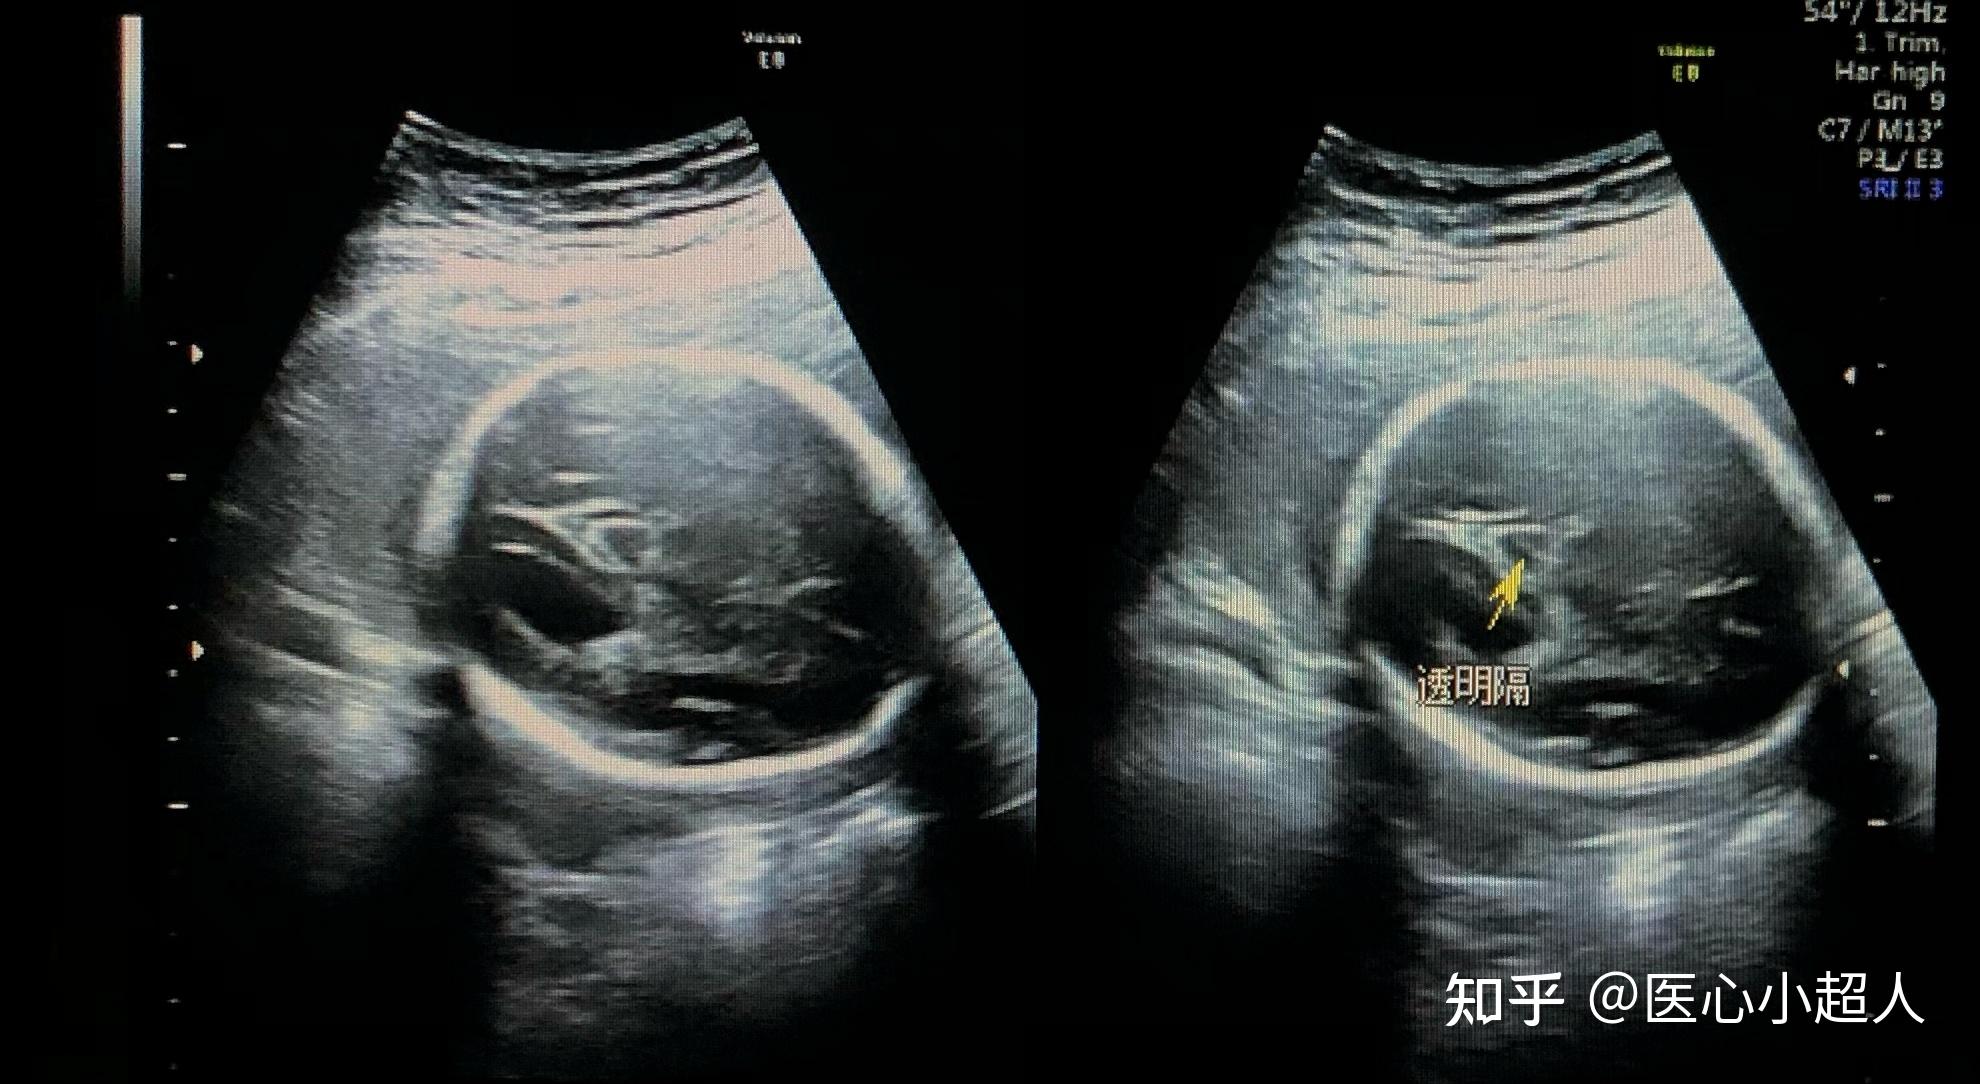

胎儿颅脑的超声所见

图片尺寸3157x2248